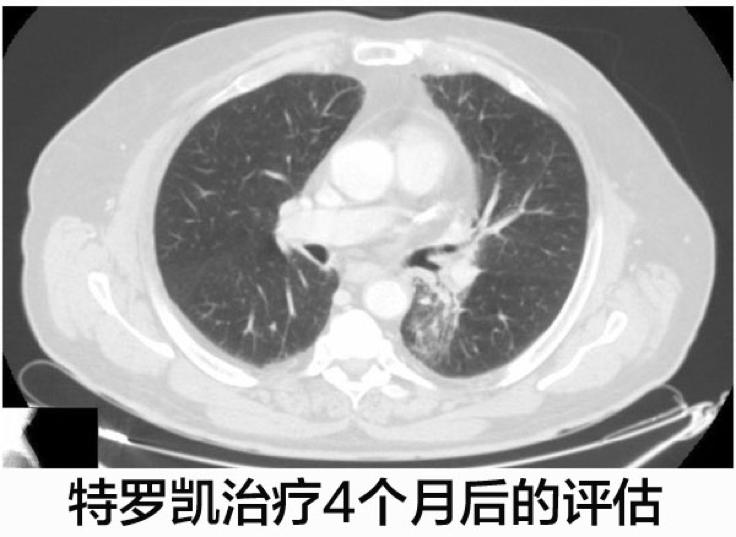

这名病人开始了厄洛替尼(特罗凯)的二线治疗,每天的计量是150mg,特罗凯治疗4个月之后CT显示肺部病灶体积减少。

患者继续使用特罗凯进行治疗,四个月之后的CT影像学检查发现左肺下叶肿瘤显著缩小,至7毫米。